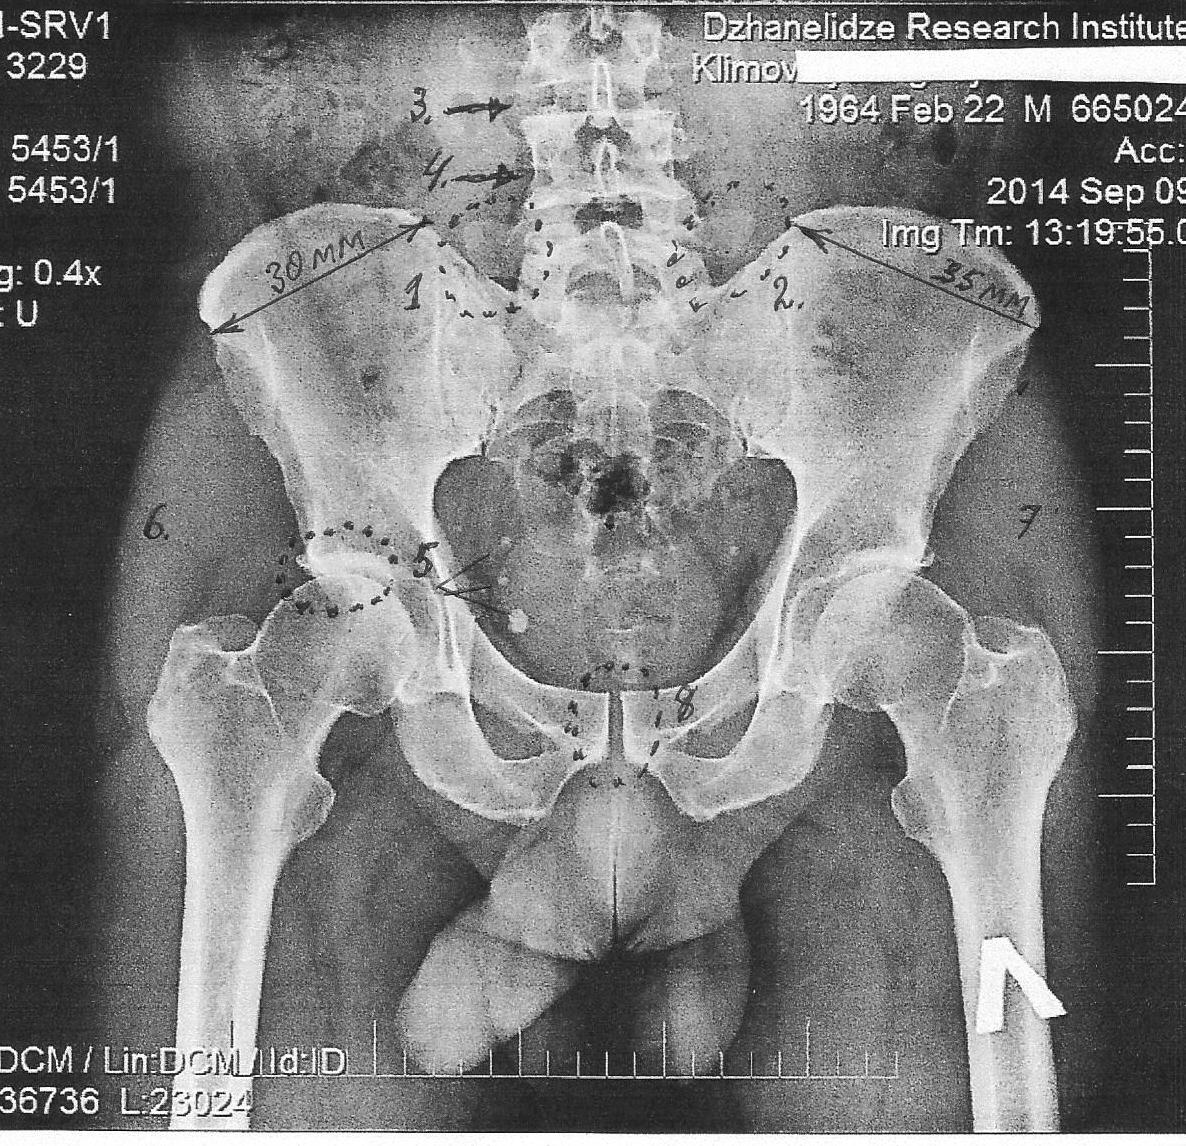

Этот снимок принадлежит моему, теперь уже бывшему, пациенту, страдавшему от болей в области спины и верхней трети правого бедра, и, как позже выяснилось, ещё и от коксартроза.

На нём хорошо просматриваются не только все костные элементы таза (в данном случае – в прямой проекции), но, что особенно ценно, и мягкие ткани и мышцы.

Начнём по порядку номеров, проставленных на снимке.

№1 и №2

Ответ: - мышцы. Это, прежде всего, мышца между правым поперечным отростком и краем подвздошной кости. Она от хронического перенапряжения и укорочения наклонила вбок тело позвонка. Естественно, что ей в этом помогали и другие мышцы позвоночного столба, например, ротаторы.

Вторая мышца – самая нижняя ветвь из группы, так называемых, подвздошно-поясничных мышц. На приведенном ниже рисунке видна часть этой мышцы (указана красной стрелкой), которая, одним концом крепится к внутреннему вертелу бедренной кости, а другим – к отростку и телу пятого поясничного позвонка.

От длительного перенапряжения эта часть мышцы укоротилась и ротировала позвонок.

№3 и №4 (там, где №4 - стрелочку надо было опустить ниже, на уровень межпозвоночного диска L4 - L5).

Если ещё раз присмотримся к телам позвонков, то увидим, щель (расположена справа) между суставными отростками пятого и четвёртого поясничных позвонков, которой не должно быть: пятый позвонок наклонён в левую (на снимке) сторону, что хорошо видно даже по направлению его остистого отростка.

Следовательно, здесь, по определению, не должно быть щели, она должна быть, но с другой стороны. Однако с другой стороны она еле-еле выражена. Могу предположить только одно – у пациента видимо имеется аномалия в развитии костного скелета. Такое бывает в нашей практике.

Мы с вами рассматривали общий обзорный снимок таза, и нам бросилось в глаза то, что не заметить - невозможно. Однако техника позволяет увеличивать снимки и видеть то, что на первый взгляд скрыто, но не менее интересно и важно.

СНИМОК -3 (увеличен)

Посмотрите на нижний край рамки снимка - он расположен горизонтально. А теперь переводим взгляд на нижние края лонных костей: левая от нас лонная кость касается линии отреза, тогда, как правая - приподнята. Эта же закономерность видна и на верхнем крае лонного сочленения - ветвь справа выше, чем с лева.

Не забывайте, что это уменьшенные размеры, по сравнению с костями живого таза. Вроде бы мелочь? Не скажите, подобная мелочь мучительно обходится больному.

Я уже упоминал о возможности наличия врождённых аномалий в данном случае, а теперь и все могут видеть одну из разновидностей аномалии развития, как правило, наследственного происхождения.

Также виден выступ на нижней части правого (на снимке – слева) поперечного отростка, наползшего на край подвздошной кости. Особенно отчётливо он виден на этом, увеличенном, снимке. О его патологической роли можно только догадываться.

Представьте себе, что пациенту надо совершить наклон вправо с разворотом влево. При этом движении поперечный отросток будет ещё больше соприкасаться с краем подвздошной кости, вызывая раздражение болевых рецепторов и боль.

Это, так называемый, эффект патологического "костного поцелуя", который больше характерен для остистых отростков в области 3,4 и 5-го поясничных позвонков (подробности в статье про юмейхо).

Хочу обратить внимание коллег и на щели подвздошно-крестцовых сочленений (ПКС), здесь они выглядят более отчётливо. Справа (на снимке) щель просматривается практически на всём своём протяжении, тогда как слева она теряется на верхней трети своего пути, указывая, что ПКС с этой стороны заблокировано. Этот факт блока было подтверждён при осуществлении специальных диагностических тестов на позвоночнике.

Кто виноват в этом? Конечно же, виноваты мышцы спины и нижних конечностей, избыточное сокращение которых привели к избыточному сжатию хрящевого диска, он высох от недостатка поступления влаги, возможно – растрескался, с образованием грыжевых выпячиваний. Однако характерных болей, которые возникают при ущемлении нервов, у больного не было.

№6 и №7

Как уже писал ранее, на снимках магнитной (ядерной) резонансной томографии (МРТ или ЯМР) видны мягкие ткани. На этом снимке они также хорошо просматриваются, и для миологов (подчёркиваю – для МИОЛОГОВ!) они представляют особый интерес.

Обратите внимание, как по разному окрашены мышцы (№6 и №7), слева белый цвет интенсивнее и они (мышцы) массивнее (больше выдаются вбок, подобно сокращённому бицепсу на руке), и они более сокращены, чем справа. На процедуре мною было выявлено возвышение правой ягодичной области над левой, а снимок подтвердил этот факт по своему.

Чтобы это могло означать? Только одно – мышцы слева больные! В них больше накопилось солей и шлаков. Это, прежде всего, малая и средняя ягодичные мышцы, а ближе к наружному вертелу ещё и напрягатель широкой фасции бедра.

При работе с пациентом эти все перечисленные в статье мышцы отличались избыточной плотностью, крайней степенью болезненности, и они очень медленно поддавались лечению.

Предполагаю, что они содержат в себе соли молочной кислоты (лактаты) и соли кальция. И эти образования расположены в грушевидной мышце, она как раз берёт начало от поверхности крестца и крепится к большому вертелу бедренной кости. При укорочении, она способна стягивать и блокировать движения в тазобедренном суставе.

Существует тест на грушевидную мышцу, но я забыл, когда последний раз видел этот тест положительным. Чаще всего приходилось регистрировать лишь чрезмерную её жёсткость, которая, по всеобщему предположению, может давить на лежащий под нею седалищный нерв, вызывая пресловутую невралгию -"ишиас".

Все перечисленные мышцы при своей патологии укорачиваются, стремясь зажать головку тазобедренной кости в вертлужной впадине подвздошной кости, приводя сустав вначале к гипотрофии, а затем и к дегенеративным изменениям, то есть, к коксартрозу.

Я не упомянул про разные величины (ширину) подвздошных костей: 30мм и 35 мм (при естественной величине таза – они превращаются уже в сантиметры!), только потому, что правой (меньшей по величине) подвздошной кости жилось куда как хуже, чем левой, из-за того, что больные мышцы не справлялись с оттоком венозной крови от неё, оставляя тазовую кость на голодном пайке.